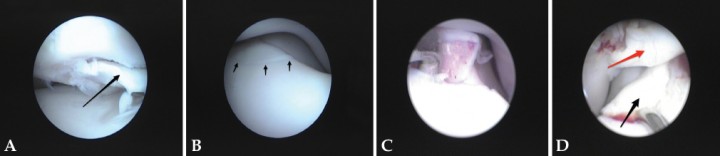

Un hallazgo interesante de nuestro trabajo ha sido el hecho de que en 72 casos (más del 25%) se observó la presencia de grandes lesiones macroscópicas cartilaginosas y subcondrales de severidad (Outerbridge modificada 4 y 5) en el área del proceso coronoides y zonas adyacentes sin que ocurrieran fragmentación o fisuras del mismo. Esta observación es muy similar a la que recogen otros estudios.[ Coppieters E, Gielen I, Verhoeven G, Van Vynckt D, Van Ryssen B. Erosion of the medial compartment of the canine elbow: occurrence, diagnosis and currently available treatment options. Vet Comp Orthop Traumatol. 2015;28(1):9-18. [PubMed] ] Recientemente algunos autores han acuñado el término “Erosión del Compartimento Medial” para referirse a esta forma de la enfermedad.[ Coppieters E, Van Ryssen B, van Bree H, et al. Computed tomographic findings in canine elbows arthroscopically diagnosed with erosion of the medial compartment: an analytical method comparison study. Vet Surg. 2015;44(4):511-20. [PubMed] , Coppieters E, Gielen I, Verhoeven G, Van Vynckt D, Van Ryssen B. Erosion of the medial compartment of the canine elbow: occurrence, diagnosis and currently available treatment options. Vet Comp Orthop Traumatol. 2015;28(1):9-18. [PubMed] ] Según estos autores existen dos formas de este síndrome: la concomitante, que aparece en presencia de otras lesiones (coronoides fragmentado / OCD), y la primaria, en la que no aparece más patología que la propia erosión (Figs. 9A-9B). Esta última suele ocurrir en animales de cierta edad y es muy difícil de diferenciar radiográficamente, ya que el único signo sería una osteofitosis más o menos severa. Ni siquiera la tomografía es capaz de visualizar estos casos con fiabilidad, en los que se debe recurrir a signos indirectos (colapso del espacio articular, esclerosis del hueso subcondral)[ Coppieters E, Van Ryssen B, van Bree H, et al. Computed tomographic findings in canine elbows arthroscopically diagnosed with erosion of the medial compartment: an analytical method comparison study. Vet Surg. 2015;44(4):511-20. [PubMed] ] más que a la observación directa del cartílago articular, que es donde reside esta patología. En medicina humana[ Waldt S, Bruegel M, Ganter K, et al. Comparison of multislice CT arthrography and MR arthrography for the detection of articular cartilage lesions of the elbow. Eur Radiol 2005; 15: 784-791. [PubMed] ] y veterinaria[ Samii V, Dyce J, Pozzi A, et al. Computed tomographic arthrography of the stifle for detection of cranial and caudal cruciate ligament and meniscal tears in dogs. Vet Radiol Ultrasound 2009; 50: 144-150. [PubMed] ] se ha usado la tomografía-artrografía para hacer resaltar el cartílago con resultados aceptables.

<p>(<strong>A</strong>) Imagen de artrografía del mismo animal de la Figura 6 después de unos meses de evolución. Ejemplo de Erosión del Compartimento Medial Concomitante. Extracción de un pequeño fragmento de coronoides en un Golden Retriever de 15 meses. El cartílago del resto de compartimento medial cubital muestra lesiones de grado 3 y 4 (flechas negras), y el húmero ha desarrollado una “kissing lesion” (lesión por fricción) (flecha azul). (<strong>B</strong>) Imagen de artrografía. Ejemplo de Erosión del Compartimento Medial Primaria. No existen lesiones de OCD ni fragmentación del proceso coronoides. Demarcación clara entre el compartimento medial y el lateral sano (flechas negras). Lesiones profundas del cartílago de la cabeza radial (flechas azules).</p>

Figura 9

(A) Imagen de artrografía del mismo animal de la Figura 6 después de unos meses de evolución. Ejemplo de Erosión del Compartimento Medial Concomitante. Extracción de un pequeño fragmento de coronoides en un Golden Retriever de 15 meses. El cartílago del resto de compartimento medial cubital muestra lesiones de grado 3 y 4 (flechas negras), y el húmero ha desarrollado una “kissing lesion” (lesión por fricción) (flecha azul). (B) Imagen de artrografía. Ejemplo de Erosión del Compartimento Medial Primaria. No existen lesiones de OCD ni fragmentación del proceso coronoides. Demarcación clara entre el compartimento medial y el lateral sano (flechas negras). Lesiones profundas del cartílago de la cabeza radial (flechas azules).

En nuestro estudio, el grado avanzado de deterioro en el cartílago articular tanto cubital como humeral se puso de manifiesto al valorar la escala de Outerbridge modificada. El 89% del componente cubital del compartimento medial y el 77% del humeral mostraban una degradación del cartílago igual o mayor a un grado 2. De esta manera, se determinó que el cúbito aparecía erosionado de forma muy severa hasta en un 40% de los animales (grado 4 y 5). El húmero, por su parte, sólo lo estuvo en un 20%, sugiriendo que posiblemente se trate de lesiones friccionales secundarias y que el área primeramente afectada sea el cúbito. Muchos de estos defectos de cartílago humerales se recogieron con el nombre de úlceras o erosiones de contacto (“kissing lesions”) (Fig. 11), aunque la mayoría de nuestros casos mostraban una gran extensión afectada. No hemos encontrado en la literatura descripciones tan detalladas de estas lesiones discriminando la parte humeral de la cubital.

<p>Imagen de artrografía. Desplazamiento con un palpador de un proceso coronoides fragmentado no desplazado (flecha negra). El resto del compartimento medial, sin embargo, está bien conservado a excepción del área adyacente, mostrando lesiones Outerbridge de grado 3-4. El húmero exhibe una “kissing lesion” (flecha azul).</p>

Figura 11

Imagen de artrografía. Desplazamiento con un palpador de un proceso coronoides fragmentado no desplazado (flecha negra). El resto del compartimento medial, sin embargo, está bien conservado a excepción del área adyacente, mostrando lesiones Outerbridge de grado 3-4. El húmero exhibe una “kissing lesion” (flecha azul).